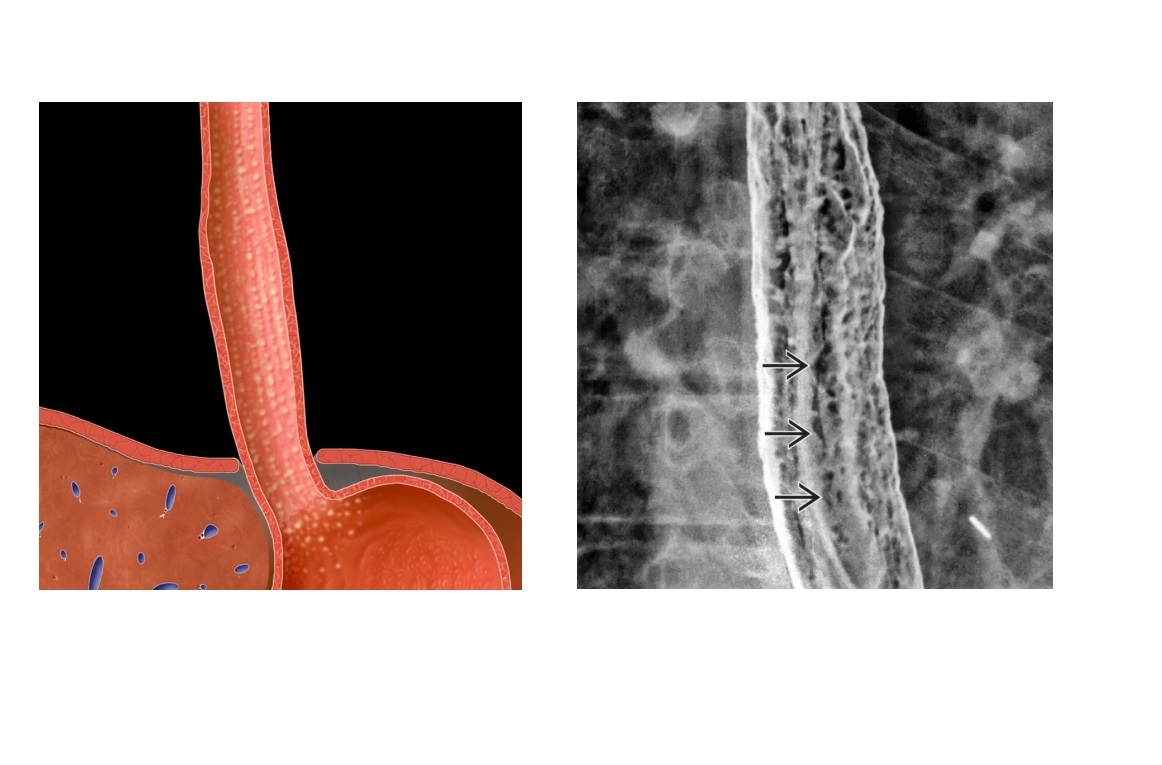

Barretts

Mid oesophageal stricture, associated hiatal hernia and reflux

‘reticular muscosal pattern’